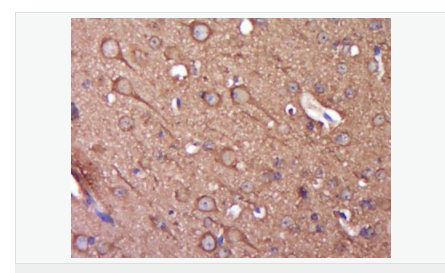

| 產品應用 | WB=1:500-2000 ELISA=1:5000-10000 IHC-P=1:100-500 IHC-F=1:100-500 Flow-Cyt=1ug/Test IF=1:100-500 (石蠟切片需做抗原修復) not yet tested in other applications. optimal dilutions/concentrations should be determined by the end user. |

| 產品介紹 | Alpha-synuclein is a member of the synuclein family, which also includes beta- and gamma-synuclein. Synucleins are abundantly expressed in the brain and alpha- and beta-synuclein inhibit phospholipase D2 selectively. SNCA may serve to integrate presynaptic signaling and membrane trafficking. Defects in SNCA have been implicated in the pathogenesis of Parkinson disease. SNCA peptides are a major component of amyloid plaques in the brains of patients with Alzheimer's disease. Alternatively spliced transcripts encoding different isoforms have been identified for this gene. [provided by RefSeq, Feb 2016].. Function: May be involved in the regulation of dopamine release and transport. Induces fibrillization of microtubule-associated protein tau. Reduces neuronal responsiveness to various apoptotic stimuli, leading to a decreased caspase-3 activation. Subunit: Soluble monomer which can form filamentous aggregates. Interacts with UCHL1. Interacts with phospholipase D and histones. Subcellular Location: Cytoplasm. Membrane. Nucleus. Cell junction, synapse. Note=Membrane-bound in dopaminergic neurons. Tissue Specificity: Expressed principally in brain but is also expressed in low concentrations in all tissues examined except in liver. Concentrated in presynaptic nerve terminals. Post-translational modifications: Note=Genetic alterations of SNCA resulting in aberrant polymerization into fibrils, are associated with several neurodegenerative diseases (synucleinopathies). SNCA fibrillar aggregates represent the major non A-beta component of Alzheimer disease amyloid plaque, and a major component of Lewy body inclusions. They are also found within Lewy body (LB)-like intraneuronal inclusions, glial inclusions and axonal spheroids in neurodegeneration with brain iron accumulation type 1. Defects in SNCA are the cause of Parkinson disease type 1 (PARK1) [MIM:168601]. A complex neurodegenerative disorder characterized by bradykinesia, resting tremor, muscular rigidity and postural instability. Additional features are characteristic postural abnormalities, dysautonomia, dystonic cramps, and dementia. The pathology of Parkinson disease involves the loss of dopaminergic neurons in the substantia nigra and the presence of Lewy bodies (intraneuronal accumulations of aggregated proteins), in surviving neurons in various areas of the brain. The disease is progressive and usually manifests after the age of 50 years, although early-onset cases (before 50 years) are known. The majority of the cases are sporadic suggesting a multifactorial etiology based on environmental and genetic factors. However, some patients present with a positive family history for the disease. Familial forms of the disease usually begin at earlier ages and are associated with atypical clinical features. Defects in SNCA are the cause of Parkinson disease type 4 (PARK4) [MIM:605543]. A complex neurodegenerative disorder with manifestations ranging from typical Parkinson disease to dementia with Lewy bodies. Clinical features include parkinsonian symptoms (tremor, rigidity, postural instability and bradykinesia), dementia, diffuse Lewy body pathology, autonomic dysfunction, hallucinations and paranoia. Defects in SNCA are the cause of dementia Lewy body (DLB) [MIM:127750]. A neurodegenerative disorder clinically characterized by mental impairment leading to dementia, parkinsonism, often with fluctuating cognitive function, visual hallucinations, falls, syncopal episodes, and sensitivity to neuroleptic medication. Brainstem or cortical intraneuronal accumulations of aggregated proteins (Lewy bodies) are the only essential pathologic features. Patients may also have hippocampal and neocortical senile plaques, sometimes in sufficient number to fulfill the diagnostic criteria for Alzheimer disease. DISEASE: Note=Genetic alterations of SNCA resulting in aberrant polymerization into fibrils, are associated with several neurodegenerative diseases (synucleinopathies). SNCA fibrillar aggregates represent the major non A-beta component of Alzheimer disease amyloid plaque, and a major component of Lewy body inclusions. They are also found within Lewy body (LB)-like intraneuronal inclusions, glial inclusions and axonal spheroids in neurodegeneration with brain iron accumulation type 1. Defects in SNCA are the cause of Parkinson disease type 1 (PARK1) [MIM:168601]. A complex neurodegenerative disorder characterized by bradykinesia, resting tremor, muscular rigidity and postural instability. Additional features are characteristic postural abnormalities, dysautonomia, dystonic cramps, and dementia. The pathology of Parkinson disease involves the loss of dopaminergic neurons in the substantia nigra and the presence of Lewy bodies (intraneuronal accumulations of aggregated proteins), in surviving neurons in various areas of the brain. The disease is progressive and usually manifests after the age of 50 years, although early-onset cases (before 50 years) are known. The majority of the cases are sporadic suggesting a multifactorial etiology based on environmental and genetic factors. However, some patients present with a positive family history for the disease. Familial forms of the disease usually begin at earlier ages and are associated with atypical clinical features. Defects in SNCA are the cause of Parkinson disease type 4 (PARK4) [MIM:605543]. A complex neurodegenerative disorder with manifestations ranging from typical Parkinson disease to dementia with Lewy bodies. Clinical features include parkinsonian symptoms (tremor, rigidity, postural instability and bradykinesia), dementia, diffuse Lewy body pathology, autonomic dysfunction, hallucinations and paranoia. Defects in SNCA are the cause of dementia Lewy body (DLB) [MIM:127750]. A neurodegenerative disorder clinically characterized by mental impairment leading to dementia, parkinsonism, often with fluctuating cognitive function, visual hallucinations, falls, syncopal episodes, and sensitivity to neuroleptic medication. Brainstem or cortical intraneuronal accumulations of aggregated proteins (Lewy bodies) are the only essential pathologic features. Patients may also have hippocampal and neocortical senile plaques, sometimes in sufficient number to fulfill the diagnostic criteria for Alzheimer disease. Similarity: Belongs to the synuclein family. SWISS: P37840 Gene ID: 6622 Database links: Entrez Gene: 6622 Human Entrez Gene: 20617 Mouse Omim: 163890 Human SwissProt: P37840 Human SwissProt: O55042 Mouse Unigene: 21374 Human Unigene: 17484 Mouse Unigene: 1827 Rat Important Note: This product as supplied is intended for research use only, not for use in human, therapeutic or diagnostic applications. Synuclein 包括α-Synuclein,β-Synuclein 和γ-Synuclein 是神經細胞中富含的前突觸蛋白。α-Synuclein,Alzheimer’(AD)病淀粉樣蛋白沉積的成份之一,集中分布在神經細胞的包體和突觸。在帕金森病人中發(fā)現有α-Synuclein的變異型,而γ-Synuclein與軸突病理學有關。此抗體將為Lewy小體癡呆癥、Parkinson癥、AD和其它一些神經性疾病提供有用的病理診斷。 |